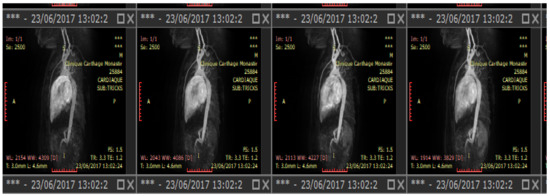

6.1. Model of the Geometry of the Descending Aorta in 3D

In this section, we proceed to the first phase of our 5D model, which consists of defining the geometry of the descending aorta in 3D. This step states the reconstruction of the aortic model from the TRICKS sections, as shown in Figure 5.

Figure 5.

Sample of TRICKS cuts for 2500 s of acquisition.

The multiplanar reconstruction in Figure 6 is a crucial step in the 3D reconstruction of the descending aorta presented in the axial plane in Figure 7.

Figure 6.

Multiplanar reconstruction of TRICKS cuts for the aorta.